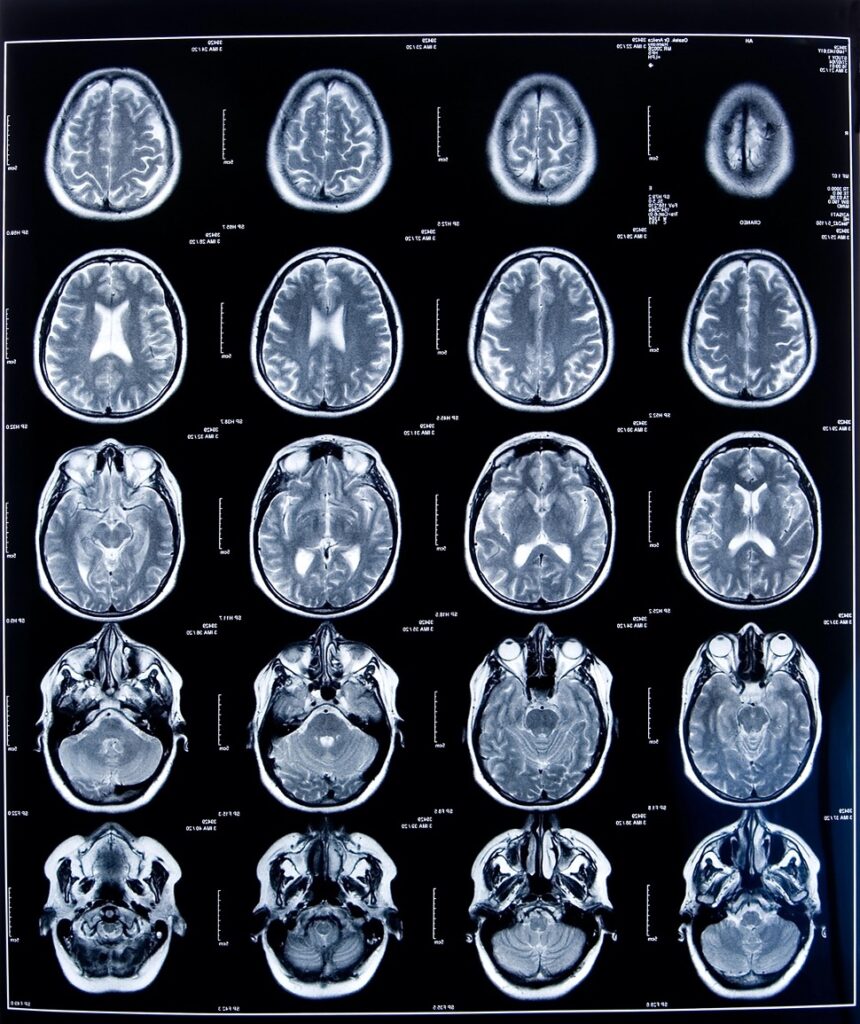

La imagen por tomografía por emisión de positrones con trazadores de tau (Tau-PET) emerge como una herramienta diagnóstica altamente sensible y específica para la detección temprana del Alzheimer. En este estudio global —el mayor hasta la fecha— se analizaron más de 6.500 sujetos de 13 países distintos, utilizando métodos ya aprobados por la FDA y la EMA para aplicación clínica.

Los datos muestran que el 10% de adultos mayores asintomáticos de aproximadamente 75 años ya presentan acumulaciones patológicas de tau. El riesgo de desarrollar deterioro cognitivo leve o demencia en pacientes con acumulaciones concomitantes de tau y amiloide se eleva al 57% en cinco años, alcanzando el 70% si ya presentan síntomas subjetivos de memoria.

La técnica demuestra relevancia clínica al ofrecer información sobre el estadio de la enfermedad y su probable evolución a corto y mediano plazo.

Aunque los biomarcadores plasmáticos ofrecen accesibilidad y valor predictivo para el depósito de amiloide, el Tau-PET permite una estratificación de riesgo más precisa y una mejor selección para ensayos clínicos terapéuticos.

Con una capacidad para predecir conversión clínica y cuantificar progresión neuropatológica, Tau-PET podría convertirse en pilar central en el manejo diagnóstico y pronóstico del espectro amiloide-tau.